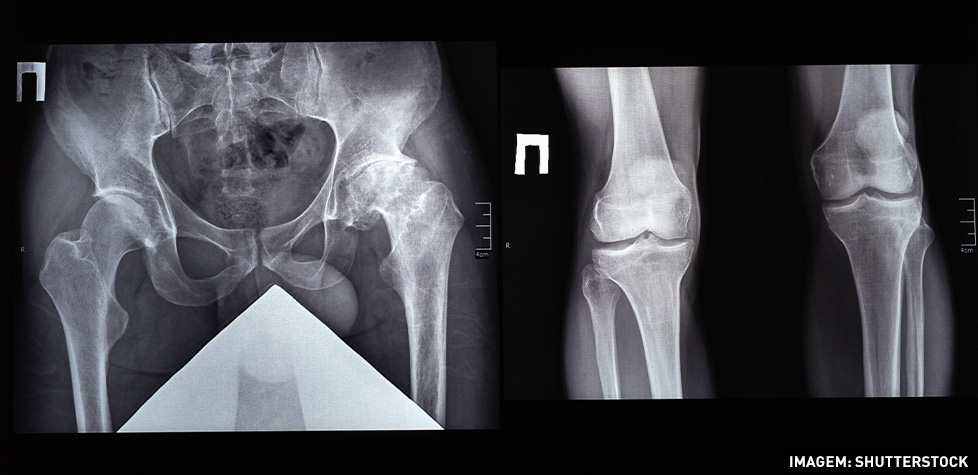

O diagnóstico geralmente envolve o exame físico: avaliação da estabilidade da rótula e testes específicos para detectar desalinhamentos ou défices musculares. Exames de imagem: radiografias, ressonância magnética (MRI) com relações patelo femorais ou tomografia computadorizada (TC) para avaliar ao pormenor a anatomia e detectar possíveis lesões nos tecidos moles e ainda da cartilagem que surgem quase sempre após a primeira luxação.